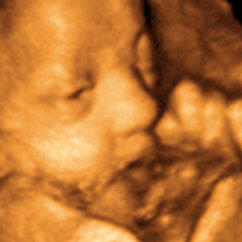

3D BabyVision London Ultrasound On A Channel London - YouTube

3D BabyVision London was featured on the A Channel news as a creative way for a favourite weather reporter to inform her viewers of her pregnancy! www.3dbaby.ca ... View Video

3D BabyVision London Ultrasound Commercial - YouTube

This 3D BabyVision London Commercial airs on the local TV station in London Ontario. www.3dbaby.ca. ... View Video